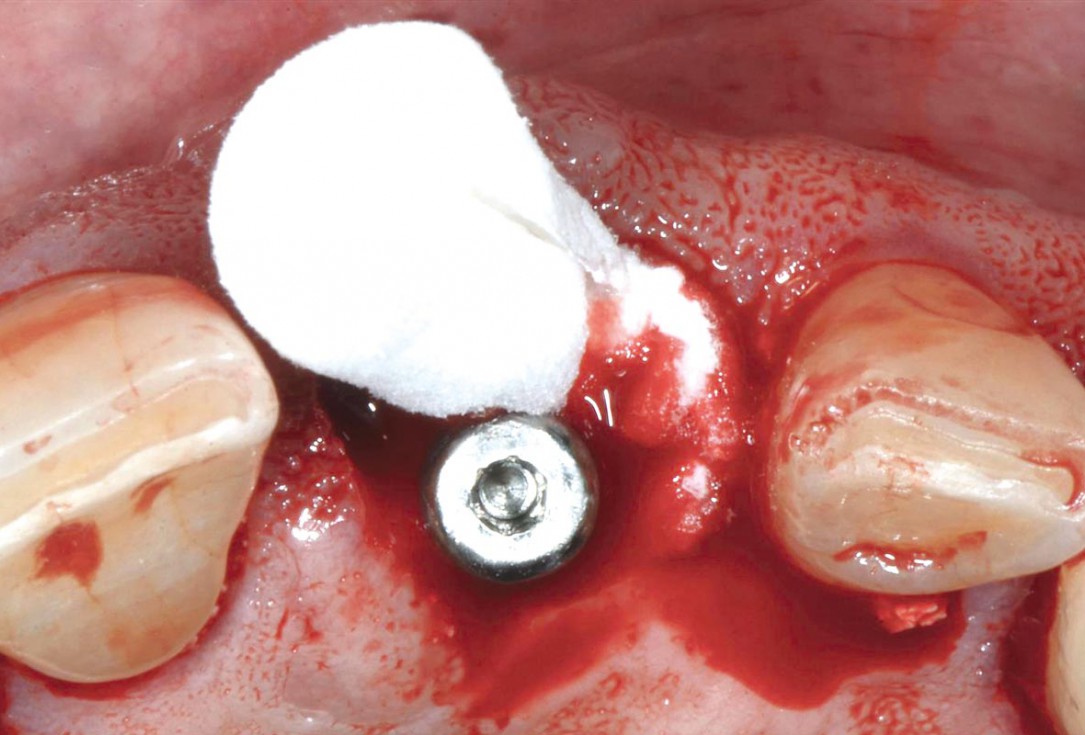

Immediate implantation with maxresorb® inject - Dr. D. Jelušić